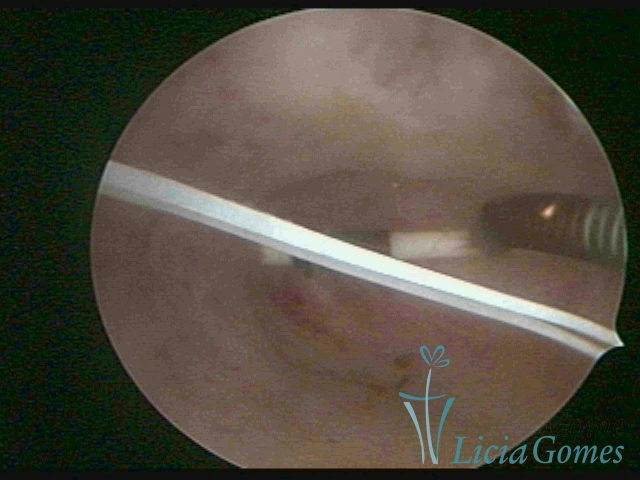

DIU perfurado miométrio

×